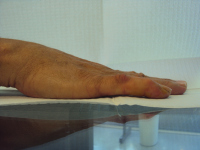

Case 1.

40 year old right handed man with several year history of

minimal bilateral Dupuytren disease. The left small finger

has reached a point of functional impairment from combined

proximal and distal interphalangeal joint contractures.